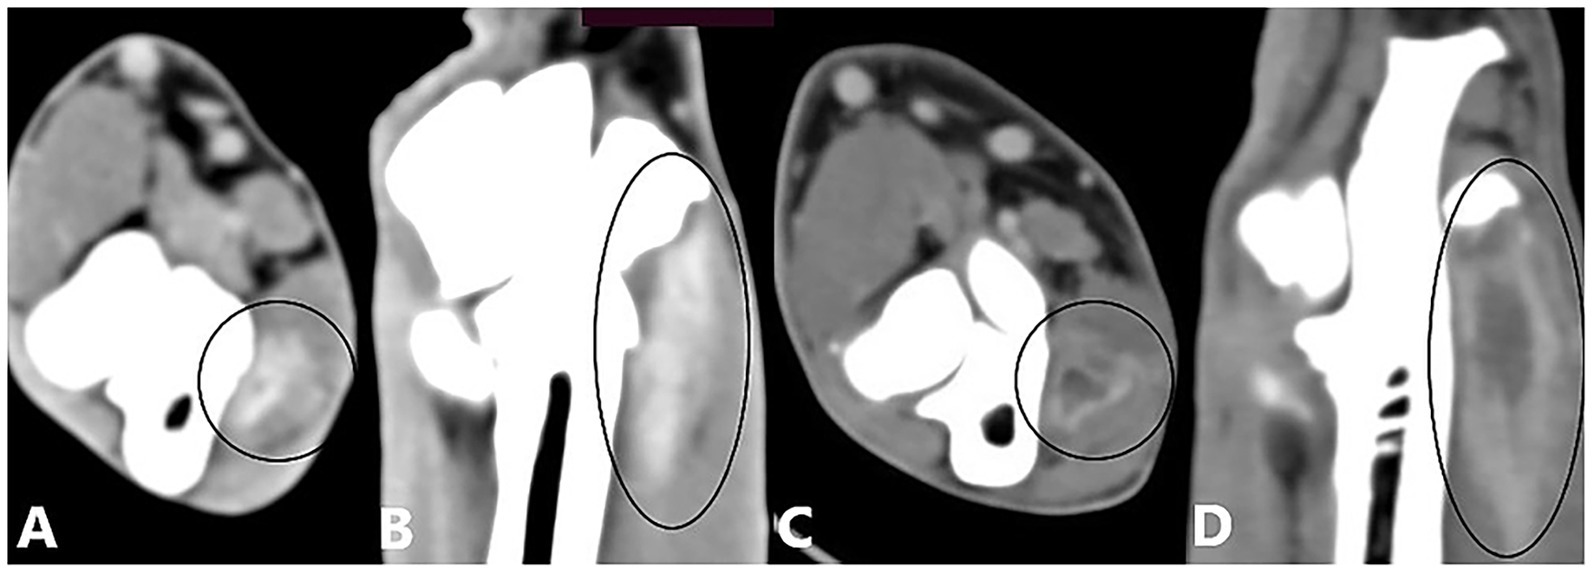

CT images obtained after contrast administration were examined in the soft-tissue window to identify enhancement of the joint capsule, one or more flexor muscles, or their origin tendons. The degree of enhancement was not considered in the analysis. Enhancement of the joint capsule was defined as a hyperattenuated periarticular area (Figure 1). Enhancement of the flexor muscles was defined as a hyperattenuated area within the flexor muscles or their origin tendons, or as a hypoattenuated center surrounded by a hyperattenuated rim (Figure 2). Joint capsule and flexor muscle enhancement could occur simultaneously in a single joint. Because of the high sensitivity of CT imaging in detecting flexor enthesopathy, elbow joints with flexor muscle enhancement were considered to have flexor enthesopathy (12). The control group, used for comparison with diseased elbow joints, comprised the elbow joints of included dogs that showed no evidence of periarticular osteophytes on radiography or CT in the bone window, no lameness (contralateral joints), and no contrast enhancement.

Figure 2. Computed tomography slices after contrast agent administration showing enhancement of the flexor muscles. (A,B) Transverse and dorsal CT slices of a right elbow joint showing a hyperattenuated zone (contrast enhancement) in the flexor muscles (black circle). (C,D) Transverse and dorsal CT slices of a right elbow joint showing enhancement of the flexor muscles, visible as a hypoattenuated center surrounded by a hyperattenuated rim (black circle).